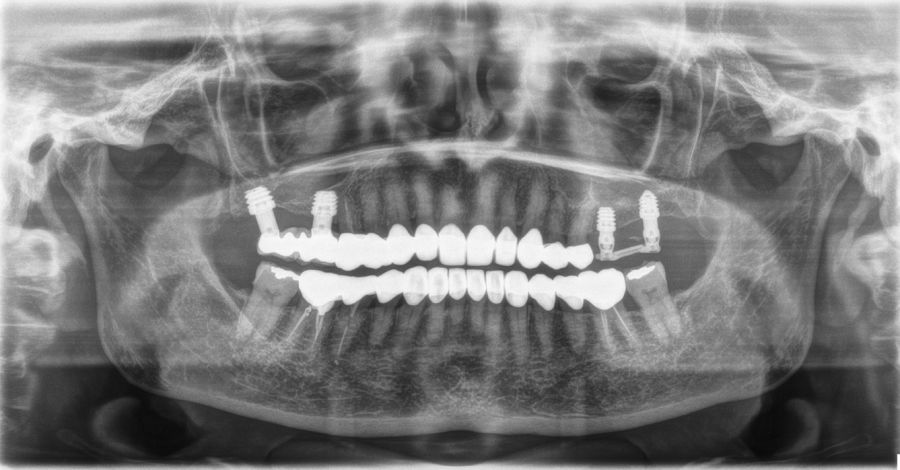

En las Figuras 5-16 se muestra uno de los casos incluidos en el estudio.

La inserción de los implantes fue realizada por un mismo cirujano, mediante la técnica de fresado biológico, a bajas revoluciones, sin irrigación. Con esta técnica todo el hueso recolectado es embebido en PRGF-Endoret durante la cirugía para posteriormente ser utilizado como injerto óseo particulado17-19. El fresado final de la cortical sinusal se realizó con la fresa de corte frontal (ideada para esta técnica) que permite la retirada del suelo del seno maxilar sin dañar la membrana de Schneider6-7. Una vez la membrana es accesible mediante la perforación crestal, se despega, se inserta el implante con el motor quirúrgico fijado a 25 Ncm y 25 rpm finalizando la inserción del implante con la llave dinamométrica (Figura 1). El implante eleva lentamente la membrana a la vez que es insertado en el neo-alveolo.

Una vez finalizada la cirugía se realiza una radiografía periapical con paralelizador, que se utilizó como punto de partida. Los pacientes acudieron posteriormente para la realización nuevas radiografías de control, tomadas con la misma técnica y sobre las que se realizaron las mediciones necesarias para comprobar la estabilidad y pérdida ósea crestal de los implantes. La medición de la pérdida ósea marginal se realizó en la última radiografía periapical realizada con posicionador de seguimiento. Una vez obtenida la radiografía en formato digital es calibrada mediante un software específico (ImageJ software- Rasband, W.S., ImageJ, U. S. National Institutes of Health, Bethesda, Maryland, USA, https://imagej.net/ij/, 1997-2018) a través de una longitud conocida en la radiografía como es el implante dental. Una vez se introdujo la medida de calibración, el programa informático realiza un cálculo basado en esta medida para eliminar la magnificación, pudiendo realizar mediciones lineales exentas de este error (Figura 2). La pérdida ósea de los implantes fue medida en dos puntos: mesial y distal en cada uno de los casos (Figura 3).

Fueron reclutados 13 pacientes que cumplieron los criterios de inclusión en los que se insertaron 30 implantes. La edad media fue de 70 +/- 1 años en el momento de la cirugía y 10 de los pacientes fueron hombres. El tiempo medio de seguimiento desde la carga fue de 126 meses (+/- 1,79; Rango 120- 150 meses). Los diámetros, longitudes y posiciones de los implantes se muestran en la Figura 4. La altura media de la cresta residual fue de 4,86 mm (+/-0,97; rango 1,95-5,88 mm). El torque de inserción medio de los implantes fue de 26,45 Ncm (+/- 1,89). Una vez insertados y cargados los implantes, la altura media final fue de 9,68 mm (+/- 2,66; rango 6,74-13,11 mm), lo que supone una ganancia promedio de 5 mm. A los 10 años, se observa una disminución media de la altura ósea ganada en los implantes en conjunto de 0, 29 mm (+/- 0,77).

La media de la pérdida ósea mesial fue de 0,73 mm (+/- 0,75 mm) y la media de la pérdida ósea distal fue de 0,98 mm (+/- 1,2 mm). No existió ningún fracaso en los implantes estudiados, por lo que la supervivencia fue del 100%. Todas las prótesis se rehabilitaron de forma atornillada mediante transepitelial, siendo un 85% de ellas puentes de 2 a 4 unidades y el resto prótesis completas. No se produjeron complicaciones en la técnica quirúrgica en ninguno de los casos estudiados, sin producirse ninguna perforación de la membrana de Schneider.